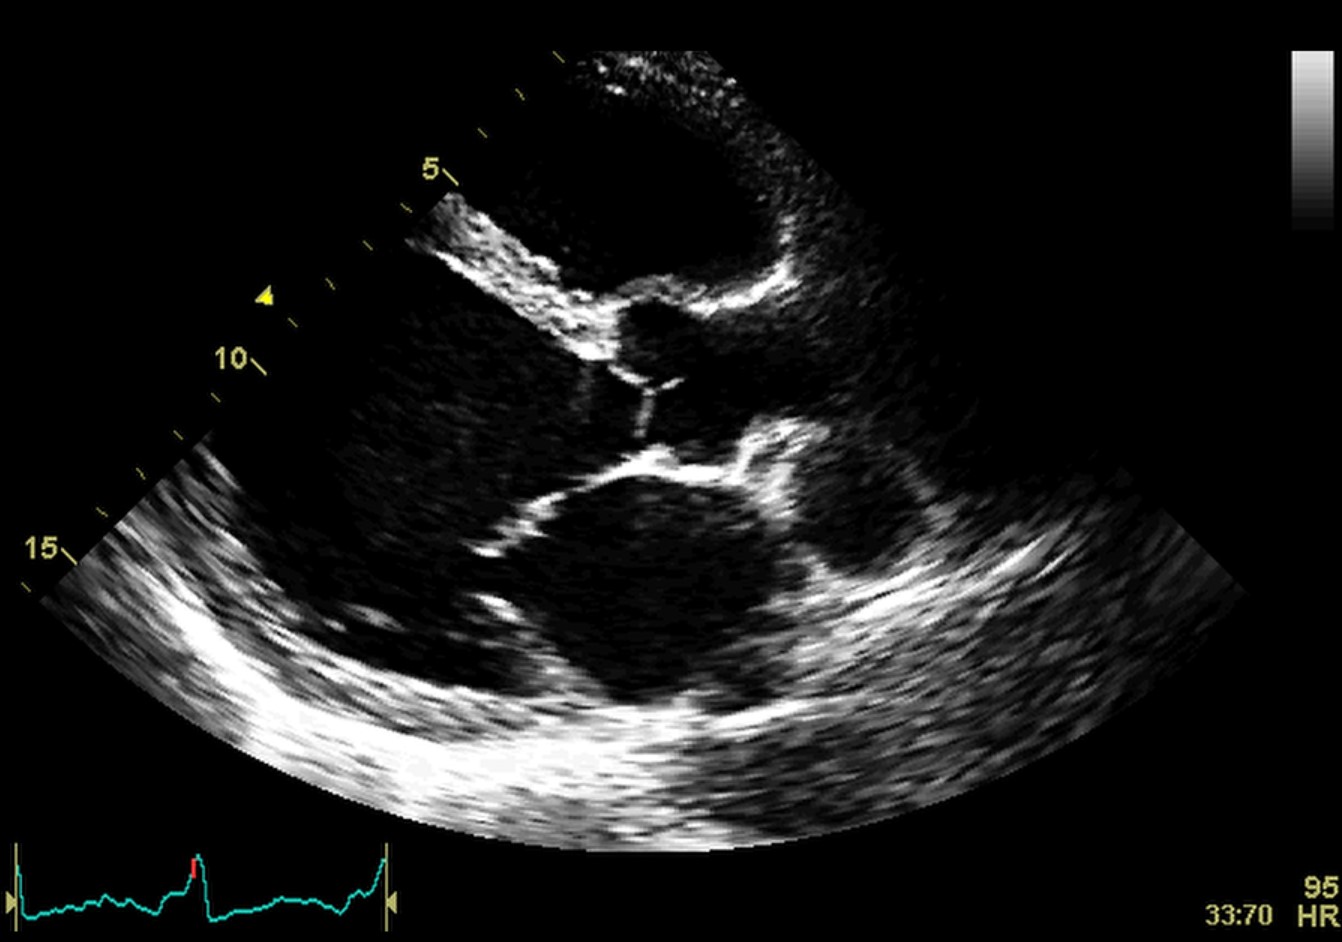

Fig. 2.Echocardiographic aspect of DCM in a patient with idiopathic dilated cardiomyopathy. (A) Parasternal short axis at the level of the mitral valve, diastolic frame showing a dilated left ventricle. (B) Parasternal short axis at the level of the mitral valve, systolic frame showing the small difference between the end-diastolic and end-systolic diameter of the left ventricle due to reduced contractility.